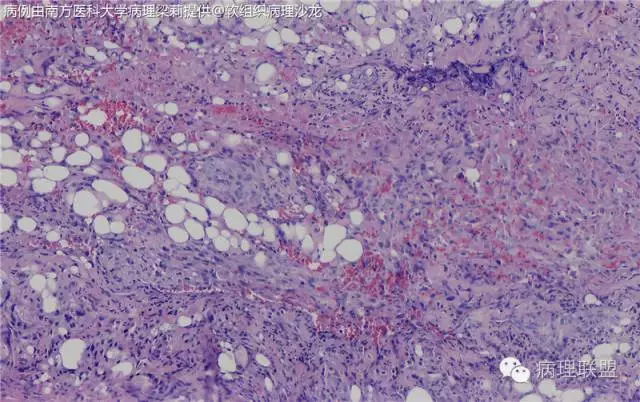

这例我们发的是卡波西样血管内皮细胞瘤,考虑如下:(1)新生儿,肢体肿物;(2)位置深,侵及皮下脂肪;(3)大多是裂隙状血管,也有少量吻合的血管网,细胞有异形,可见坏死

而复合性血管内皮瘤则是由良性、中间性和恶性的成份组成,也是浸润性生长,常常侵犯皮下脂肪组织,此例细胞形态由梭形细胞、卵圆形细胞及上皮样细胞组成,形态可见良性区域、中间性区域及高分化血管肉瘤或上皮样血管肉瘤区域,因此,似乎复合性血管内皮瘤更妥。此类肿瘤可以发生于婴幼儿。当然与Kaposi型血管内皮瘤一样,同属中间性血管瘤,只是后者,若肿瘤体积大,可出现Kasabach-Merritt综合征。

个人觉得应该是皮下纤维素渗出导致的内皮细胞旺炽性增生,局部呈内皮细胞乳头状增生,不认为是迷路样吻合;可能是婴幼儿血管瘤破裂诱发,也可能是血管畸形诱发。

注意活跃增生的内皮细胞总是与纤维素关系密切,并非穿插浸润的真皮胶原束。

混合型血管内皮瘤虽是混合各种形态,但是其主要成份一定是内皮瘤成份,上皮样血管内皮瘤或网状血管内皮瘤成份,其它血管肉瘤,血管瘤次要。@广医二院_病理科_梅开勇 仔细看了,好像是胶原。